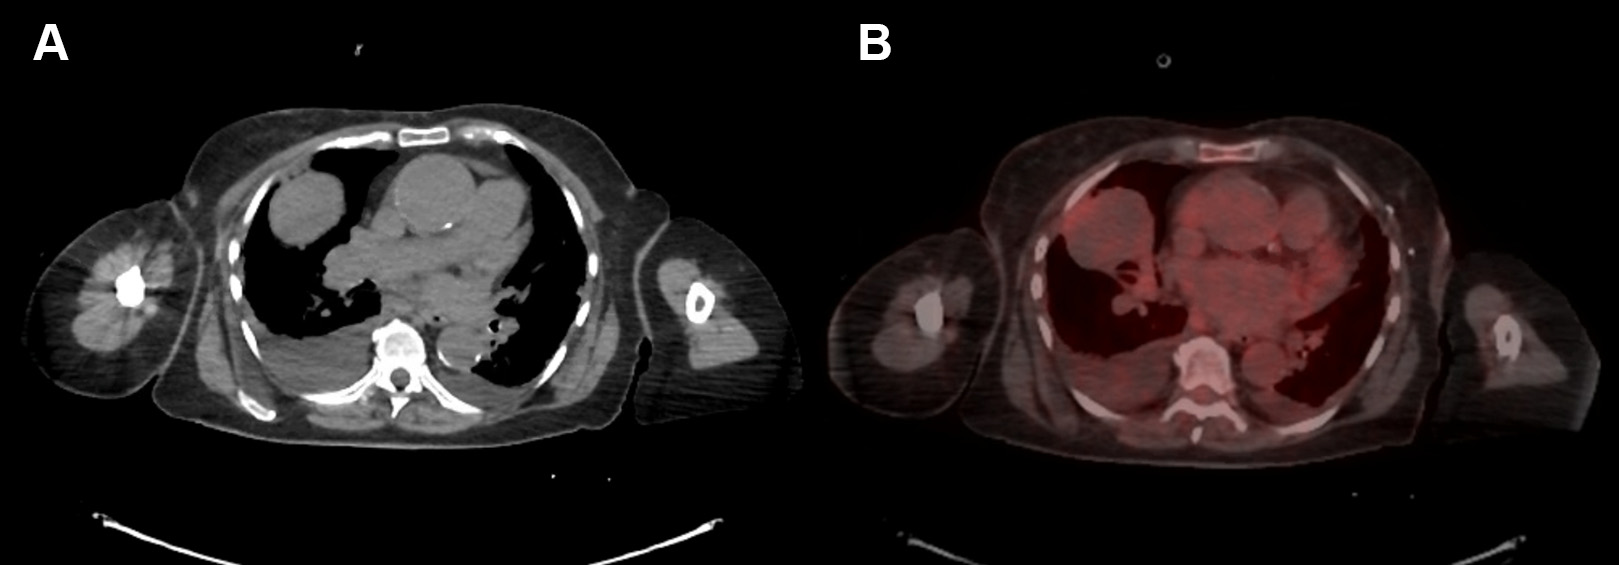

患者胸部CT扫描如下(图2A)。出院后行正电子发射计算机断层扫描成像(PET)扫描,发现右中叶肿块间歇性增大,摄取值小(标准化摄取值为3.7)(图2B)。经临床评估后,行增强CT,再次显示右侧中叶肿块,肿块明显强化(图3)。

图2 A.CT和B.PETCT扫描显示一个右中叶大肿块,活动极小及双侧胸腔积液